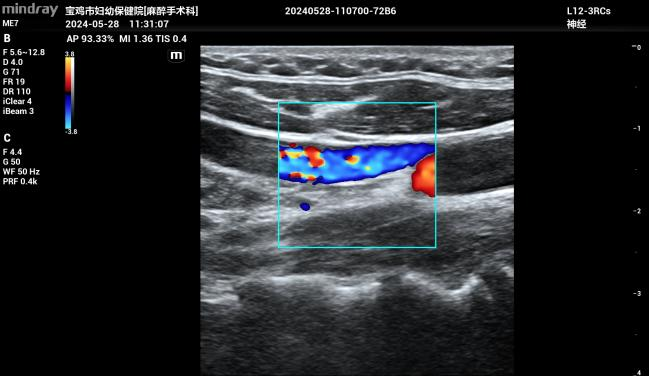

据了解,中心静脉置管术是指:经任何一条静脉插管使尖端达到上腔静脉的穿刺技术,常用穿刺部位为锁骨下静脉、颈内静脉、股静脉。对于病情危重的ICU患者,大多需要中心静脉置管,建立深静脉通道,快速输入所需药物,迅速传达全身各个组织,及时挽救和维持生命。改良式超声引导下中心静脉置管或动脉置管术是:在高频超声探头超声引导下,通过“针尖抖动法”“靶环消失征”判断穿刺进入血管的情况,实时显示血管解剖结构,清晰观察穿刺针在血管内的走向和位置。此技术特别适用于血管细小且位置较深的婴幼儿,可明显提高置管成功率,缩短穿刺时间,提升安全性,减少并发症。

据介绍,该技术是市妇幼保健院麻醉手术科主任张茂鹏在重庆医科大学附属儿童医院学习并引进开展的,目前已开展改良式超声引导下中心静脉导置管和挠动脉穿刺置管术50例。本病例是医院该技术首次应用于2.6公斤新生儿大范围肠切除吻合术,促进了小儿外科手术向更高难度进军。此技术也可应用于产科危重手术,为危重新生儿、婴幼儿、孕产妇手术提供了更为精准和安全的保障措施。